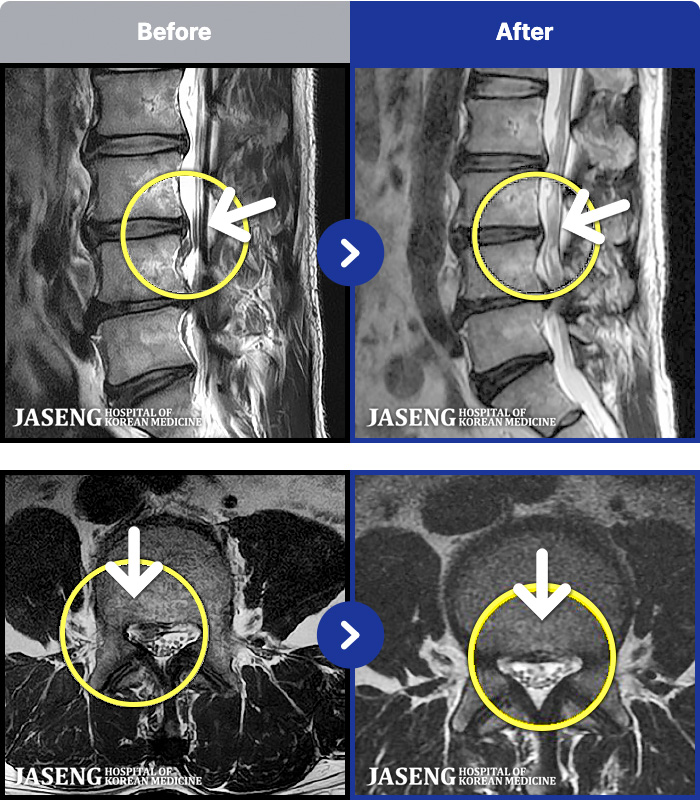

MRI ġ

54 MRI ũ ʸ Ȯϼ.

[_㸮ũ] Ͽ ü Ÿ Ͽϴ.